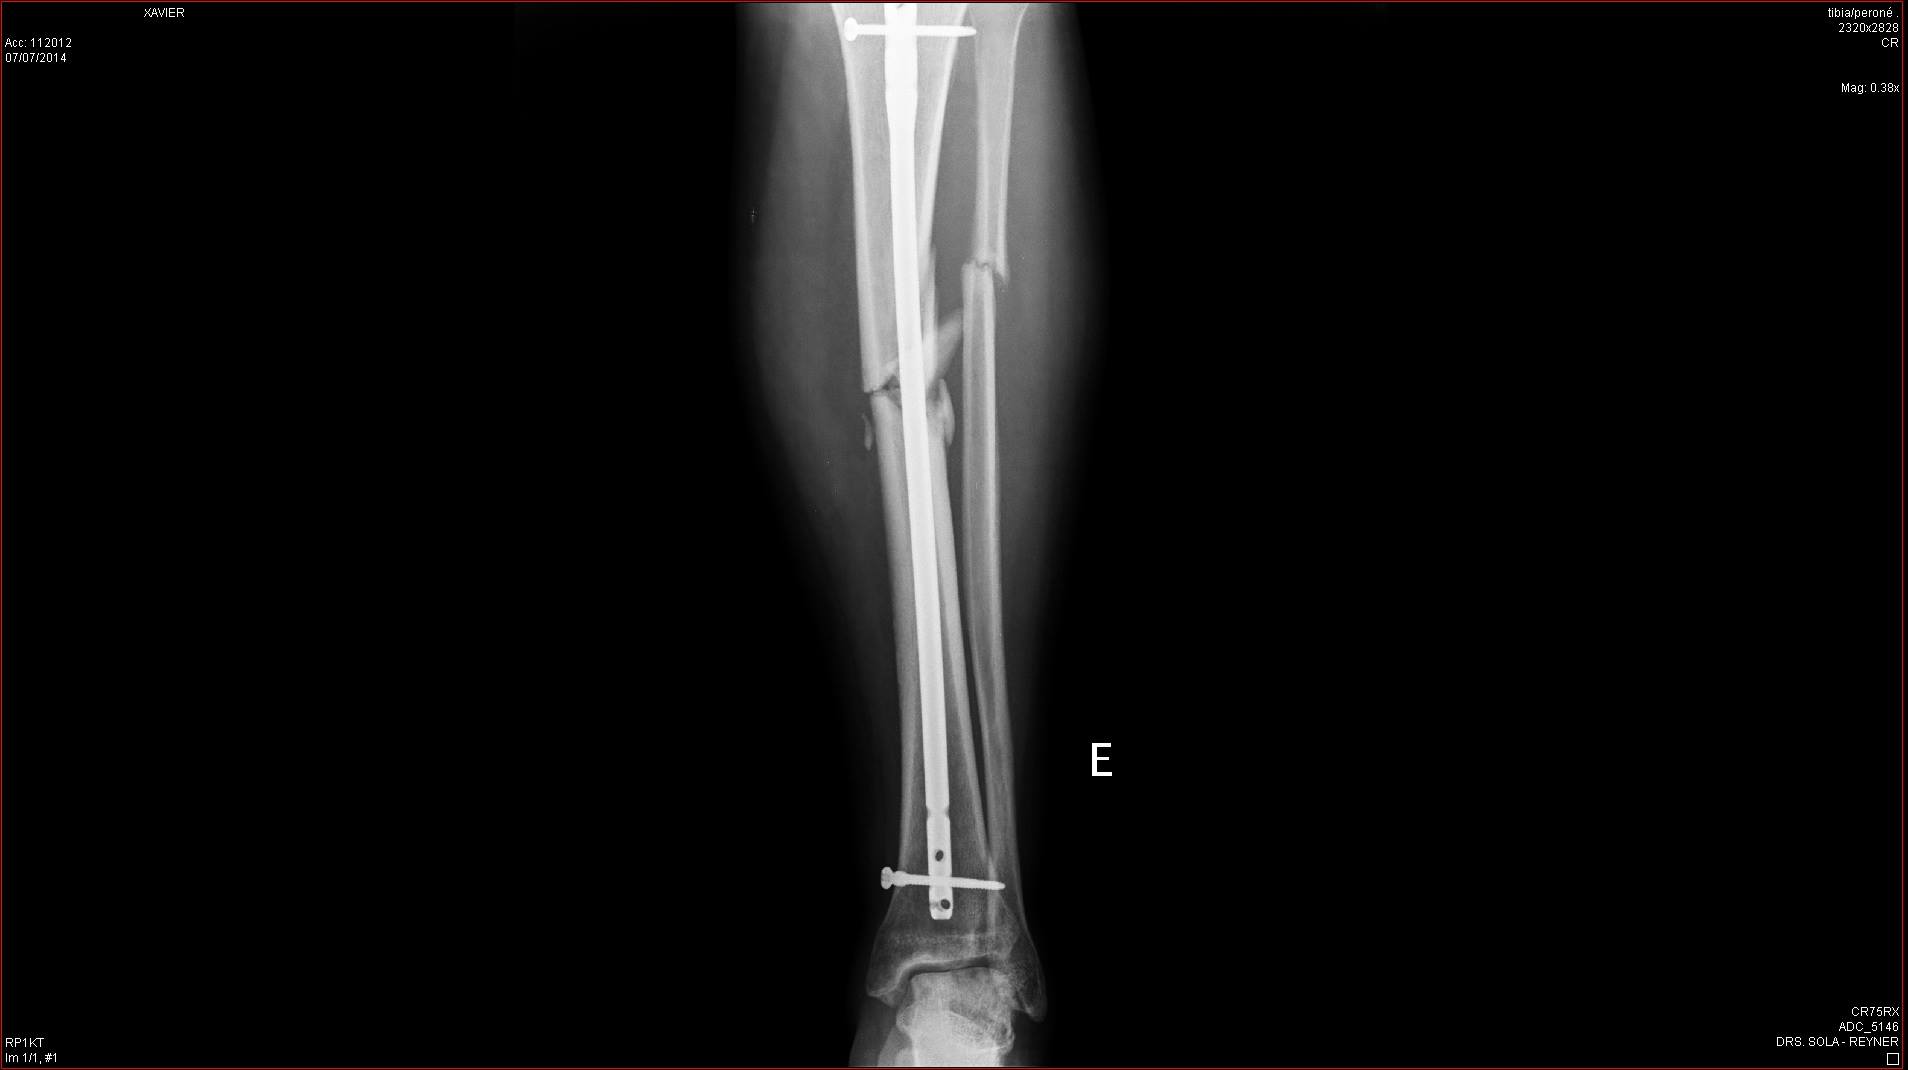

Ahora mismo es lo unico que puedo hacer, recordar los buenos momento, tengo la tibia y peroné rodas y estilladas desde hace 4 meses, más lo que me falta para volver a caminar, así que toca esperar y tener paciencia :(

Yo llevo 4 meses en el dique seco, me quedo asi la pata despues de ser atropellado en un paso de peatones por una moto que adelanto a un coche que me estaba cediendo el paso (Que aun tiene más delito!)

Despues de 4 meses aun lo tengo así

Pero como el mono es tan fuerte, ya empiezo a darle a pata coja! Ya que ni tengo ni la tibia ni peroné pegados, apenas puedo mantenerme de pie con esta pierna :(